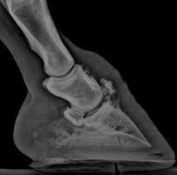

骨髄炎は血行性に、あるいは隣接感染によるものが多く、開放性骨折の場合にも発生します。

化膿性骨髄炎では、骨内に膿瘍abscessが形成される。

体の他の骨における化膿性骨髄炎では、患部の疼痛・腫脹ならびに白血球増多・赤血球沈降速度の増加・発熱などが見られます。

一般に化膿性骨髄炎は急性ですが、犬においては人におけると同様にBrodie’s abscessすなわち骨内の限局性慢性骨髄炎もあるといわれています。